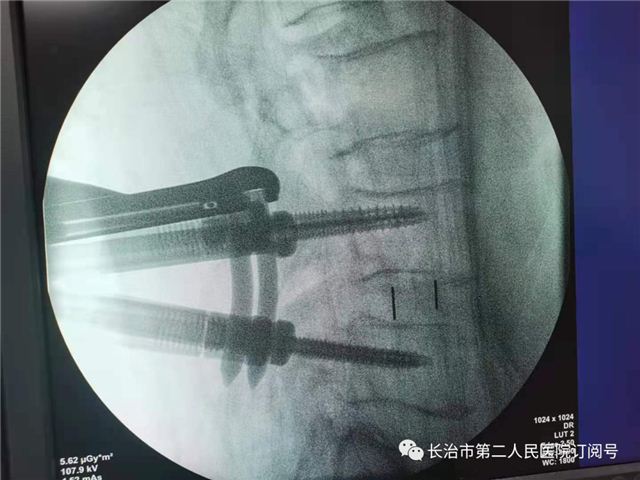

术前定位

置入通道